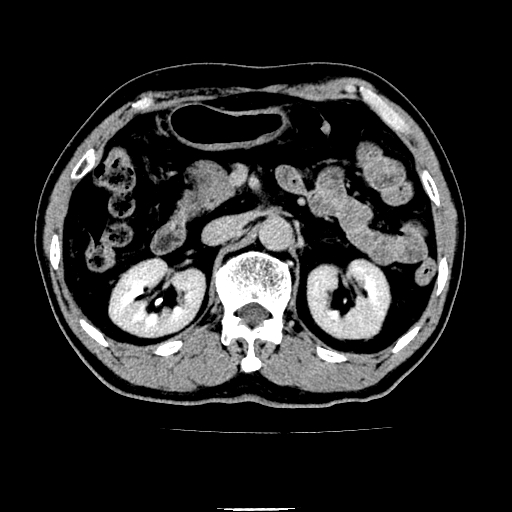

以下是引用chenqiong在2010-3-25 20:56:00的发言:[br]1、胆囊炎,胆囊息肉[br]2、肝内胆管及胆总管扩张,胆总管下端结石[br]3、十二指肠乳头旁憩室

以下是引用zxl51642在2010-3-26 10:47:00的发言:[br]胆囊炎,胆囊息肉,胆总管扩张,但未看到明显肿块,肝内胆管扩张不像恶性,炎性狭窄或阴性结石可能吧,建议mrcp,右肾小囊肿